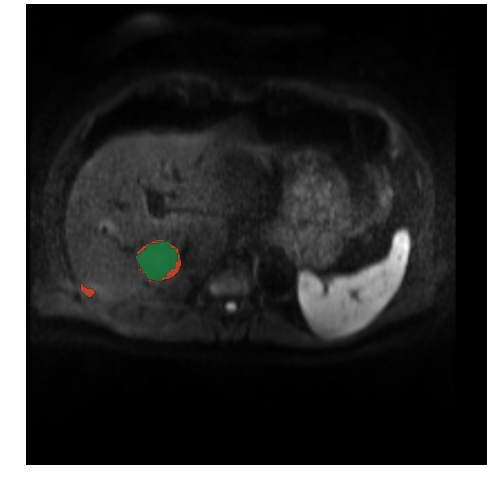

As seen in figure 8, the CFCN was able to segment the liver lesion correctly. In both cases the CFCN undersegments the lesion leading to a Dice score of 85% in both cases. The quantitative segmentation results are shown in table 1. The Cascaded U-Net was able to reach a dice score for liver in MR-DWI of 87%. For lesion we found a mean dice score of 69.7%.

Figure 8: Automatic lesion segmentation with cascaded fully convolutional neural networks (CFCN) in DW-MRI. The raw DW-MRI slices (left), were automatically segmented with our proposed method. Green depicts correctly segmented lesion pixels. Red shows false positive and false negative, i.e. all wrong predictions, of the lesions. In both cases the proposed CFCN achieves an dice score for lesions of 85%.